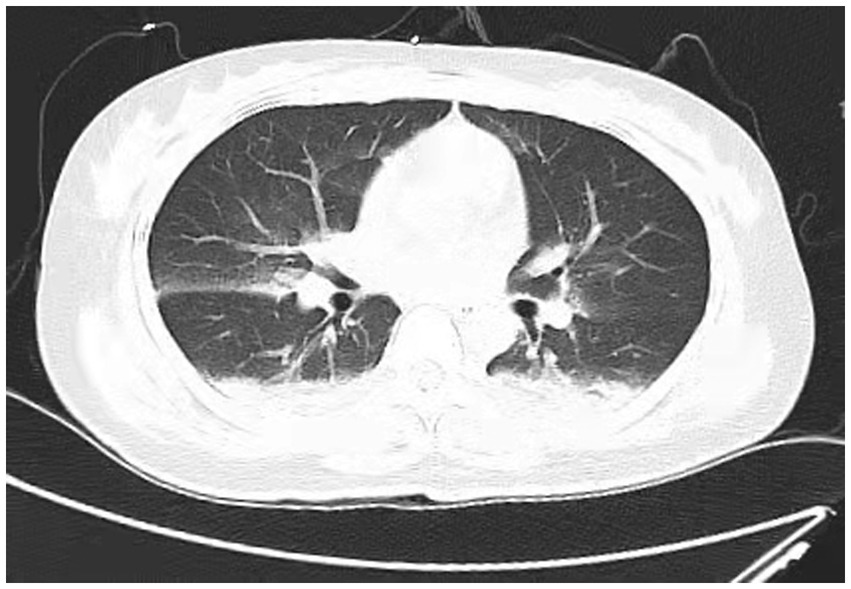

A 38-year-old married female with no previous history of cardiac disease, asthma, pneumonia, or allergies to food or medication presented with a ruptured ectopic pregnancy. On March 9, 2022, at 19:45, she underwent an emergency laparoscopic-assisted salpingectomy under general anesthesia at a local hospital. All preoperative evaluations, including laboratory tests, imaging studies, and physical examinations, were within normal limits. The surgery concluded at 21:00 without complications, and the anesthesia was satisfactory. Intraoperative fluid replacement included 1,000 mL of normal saline. At 21:10, the endotracheal tube was removed, and the patient was alert with no complaints. At 21:15, cardiac monitoring indicated a decrease in peripheral oxygen saturation (SpO2) to approximately 75%. The patient reported chest tightness and dyspnea, with pink frothy sputum. Physical examination revealed clear consciousness, tachypnea, and bilateral pulmonary rales. Immediate oxygen therapy via nasal cannula was started. Arterial blood gas analysis revealed: pH 7.31, partial pressure of arterial oxygen (PaO2) 83 mmHg, partial pressure of arterial carbon dioxide (PaCO2) 47 mmHg. A 12-lead electrocardiogram displayed sinus rhythm without signs of acute ischemia or infarction. After administration of 40 mg methylprednisolone and 20 mg furosemide intravenously, oxygen therapy was switched to a face mask, resulting in a SpO2 of approximately 95%. Due to ongoing chest tightness and dyspnea, the patient was transferred to our emergency department. Upon admission, the patient reported chest tightness and mild dyspnea. Vital signs were: temperature 37.3°C, pulse 100/min, respiratory rate 26/min, blood pressure 108/72 mmHg, SpO2 98% (with face mask oxygen). Physical examination revealed bilateral pulmonary rales, with normal cardiac and abdominal findings and no lower extremity edema. Non-invasive positive pressure ventilation was promptly initiated, along with 20 mg furosemide intravenously. Arterial blood gas analysis showed: pH 7.34, PaO2 127 mmHg, PaCO2 47 mmHg, white blood cell count 16.47*109/l, neutrophil percentage 96.6%, hemoglobin 107 g/L, platelet count 202*109/l, D-Dimmer 1.98 mg/L fibrinogen equivalent units, N-terminal pro-B-type natriuretic peptide 86.5 pg/mL. Chest computed tomography (CT) revealed bilateral pulmonary exudative changes consistent with pulmonary edema (Figure 1). After 6 h, the patient’s symptoms improved, with no dyspnea or chest pain and only a mild cough without sputum. Repeat arterial blood gas analysis showed: pH 7.46, PaO2 285 mmHg, PaCO2 45.9 mmHg. A follow-up chest CT at 12 h demonstrated significant resolution of the bilateral pulmonary exudative changes (Figure 2). Contrast-enhanced CT showed no evidence of pulmonary embolism (Figure 3). The patient’s respiratory status improved over the following days as the pulmonary edema resolved. She was discharged after 6 days without any complaints, and a final chest CT showed no significant abnormalities (Figure 4). A one-month follow-up revealed no residual symptoms.

Figure 2

Chest CT scan depicting most of the lung infiltrates resolved at 6 h after extubations. (Scattered cloud-like opacities with blurred margins are observed in both lungs).